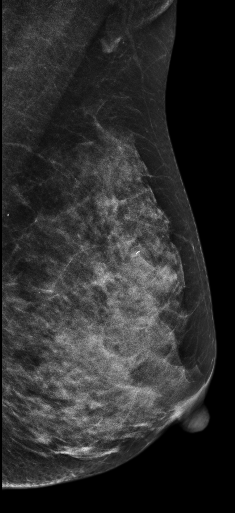

放大图像:

在常规2D图像右乳外上象限隐约见一不规则团块影,部分边界模糊(容易漏掉),边缘可见粗大钙化灶,在V-Preview图像MLO位和CC位上团块显示较模糊,但钙化清晰可见,在3D-slab图像上我们可以清晰见到病灶呈分叶状改变,边缘可见蛋壳样钙化灶,周边见细线样透亮环。从以上细微征象我们可以初步判断是一良性病灶。

病理证实左乳纤维腺瘤,此病例我们可以发现3D-Slab(厚层图像)对钙化灶形态大小显示更加清晰。